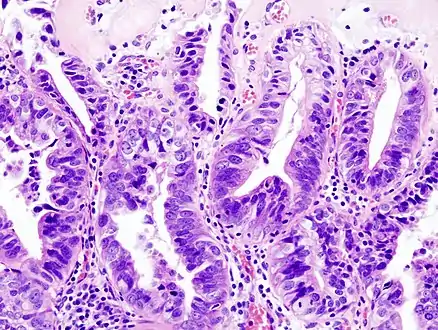

Gallbladder adenocarcinoma histopathology

Most tumors are adenocarcinomas, with a small percent being squamous cell carcinomas.